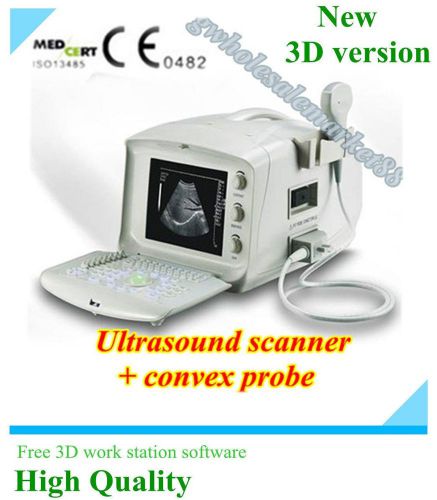

3D Portable Notebook Digital Laptop Ultrasound machine Scanner CONVEX PROBE

3D Full Digital Portable Ultrasound Scanner convex & Transvaginal 3D workstation

NEW Diagnostic Ultrasound Scanner MACHINE +3D function + convex sensor pregnancy

2015 Digital Laptop Ultrasound Scanner+Convex+ Transvaginal Probe+ 3D image-DHL